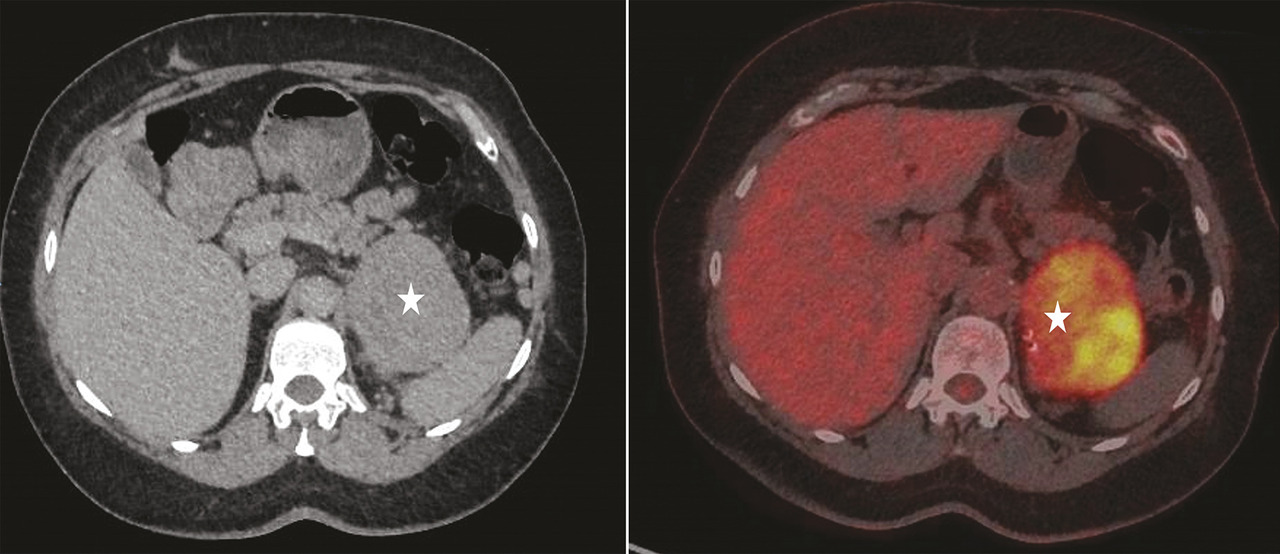

– lorsque la lésion est homogène, une densité spontanée au scanner inférieure à 10 unités de Hounsfield (UH) témoigne d’un contenu graisseux et affirme le diagnostic d’adénome cortical bénin.1 Si la tumeur mesure moins de 3 cm, le seuil de densité éliminant la malignité peut être porté jusqu’à 20 UH3, 4 (fig. 2A ) ;

– lorsque la lésion est homogène, une densité spontanée au scanner inférieure à 10 unités de Hounsfield (UH) témoigne d’un contenu graisseux et affirme le diagnostic d’adénome cortical bénin.1 Si la tumeur mesure moins de 3 cm, le seuil de densité éliminant la malignité peut être porté jusqu’à 20 UH3, 4 (

Enfin, une autonomie sécrétoire surrénalienne est plus fréquente dans les incidentalomes surrénaliens bilatéraux et particulièrement en cas d’hyperplasie surrénalienne macronodulaire (fig. 2B ).7

Enfin, une autonomie sécrétoire surrénalienne est plus fréquente dans les incidentalomes surrénaliens bilatéraux et particulièrement en cas d’hyperplasie surrénalienne macronodulaire (